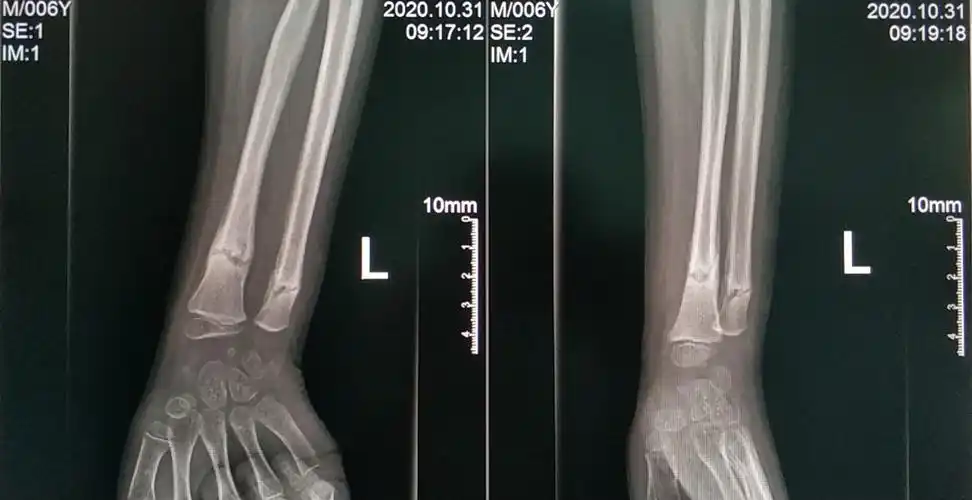

见左胫骨骨折端为纤维组织填充,无连续性骨痂,无明显的炎性渗出物

术后三个月,x光片可见骨痂形成,患者恢复良好!家属满意!继续观察!